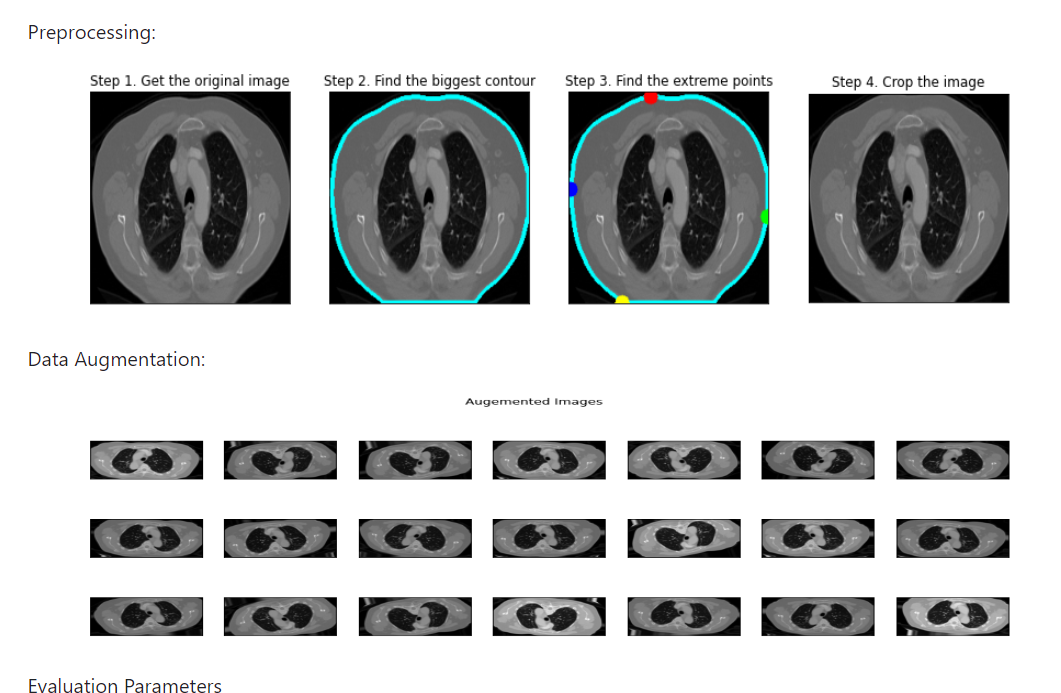

Preprocessing

To use the Chest CT Scan images in our deep learning model, we performed preprocessing to ensure they were suitable for training. This included various preprocessing steps such as resizing, normalization, and converting the images into a format compatible with our model.

Data Augmentation

Data augmentation techniques were employed to expand the size of our training dataset and enhance the robustness of our deep learning model. These techniques involved generating new training samples through transformations like rotation, flipping, and zooming.